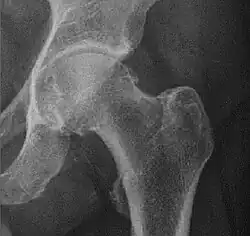

![Figure 5 (b). Coxa profunda.[3]](./X-ray_of_coxa_profunda.jpg)